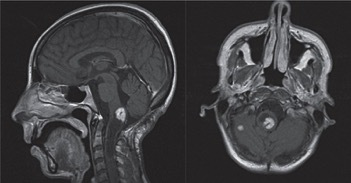

17、结核:人类感染结核杆菌的历史可以追随到几千年前。中枢神经系统结核是由牛型结核分枝杆菌引起的肉芽肿。该病主要累及脑及脑膜,引起脑膜炎和结核瘤,但偶尔也可以累及脊髓。临床症状可有头痛、发热、神志恶化及癫痫发作。

(矢状位及横断位T1WI示一环状高信号,中心呈低信号,伴病灶周围水肿。横断位T2WI FLAIR示脑干区混杂信号病灶伴瘤周水肿,横断位T1WI C示右侧脑桥环状强化病灶伴其周水肿)